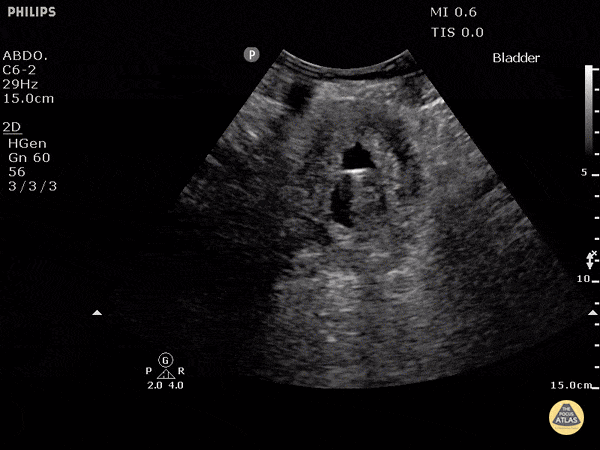

76M: Intubated Foley in, U/o dropped, ?dry

Prolate ellipsoid equation: Volume = Length x Width x Height x 0.52

Hydronephrosis

Examples: http://www.thepocusatlas.com/hydro-and-obstruction/

Evidence: https://www.nejm.org/doi/pdf/10.1056/NEJMoa1404446

Tutorial: https://westernsono.ca/screencasts/miscellaneous/hydronephrosis-tutorial/